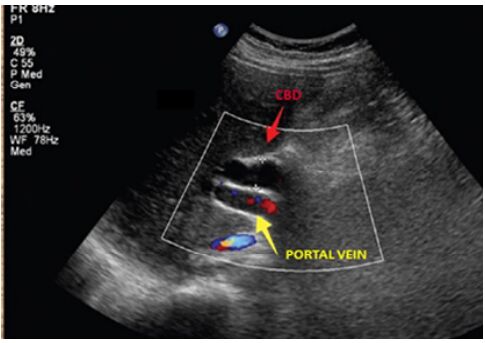

67.超音波掃描膽道時,出現如下圖雙管獵槍的特徵(double barrel shotgun sign),其最有可能的診斷為下列何者?

(A)總膽管擴張 (B)總膽管結石 (C)總膽管腫瘤 (D)門靜脈高壓